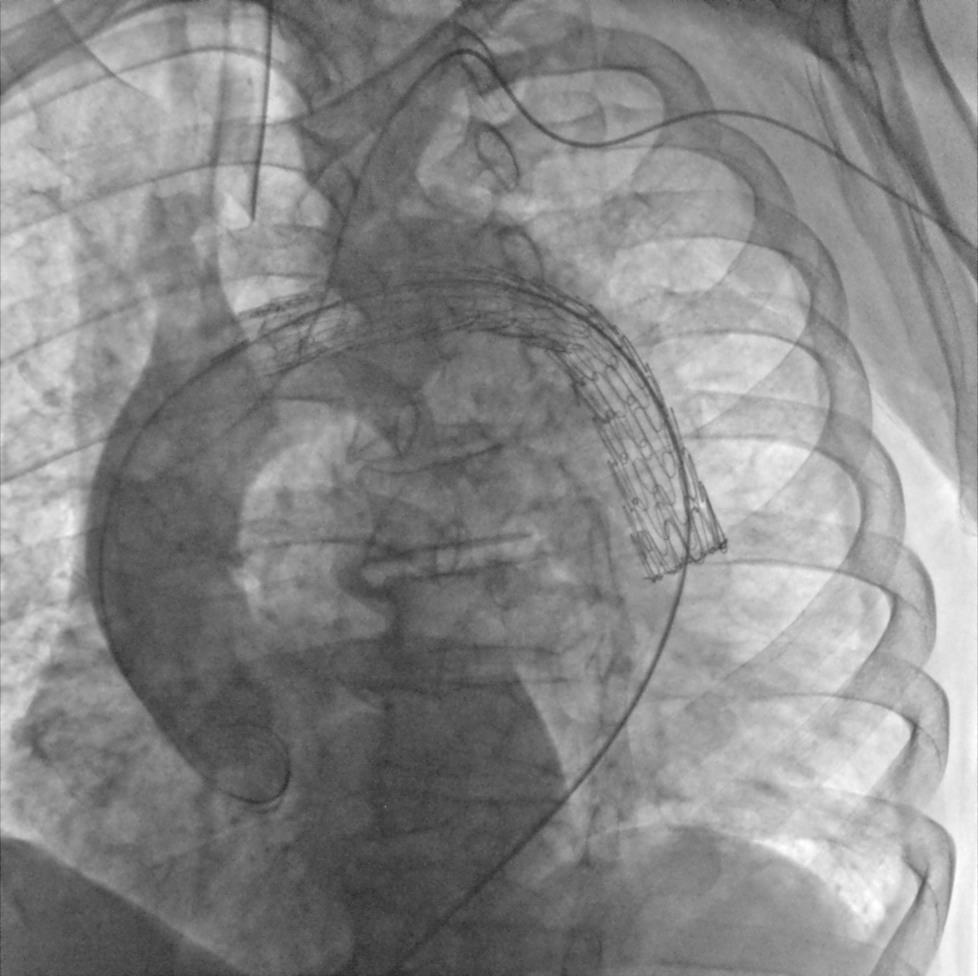

Мобильная рентгеновская С-дуга «Сапфир»

| «Сапфир» — новая мобильная С-дуга производства АО «МТЛ», предназначенная для точной диагностики во время хирургических вмешательств. Режимы работы: рентгеноскопия, рентгенография, цифровая субтракционная ангиография. | Компактная конструкция и удобное управление делают систему универсальным инструментом для операционных различного профиля, позволяя проводить как рутинные, так и специализированные процедуры. Подходит для широкого спектра исследований и хирургических вмешательств под рентгеновским контролем, включая травматологию, ортопедию, урологию, общую хирургию и обследование периферических сосудов. |

Высокое качество визуализации